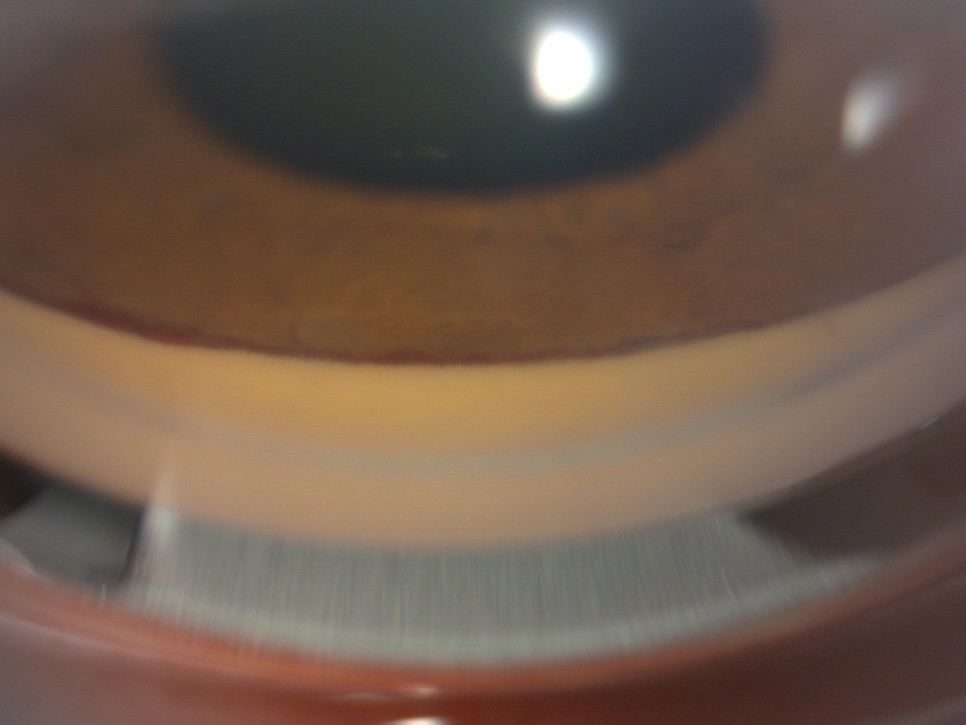

신생혈관 녹내장(NVG, neovascular glaucoma) 검사 결과 사진1. Anterior segment slit photography

홍채에 비정상적인 혈관이 보이고 맨몸에 섬유화가 진행된 부분도 보인다. 주름이 안쪽으로 말려 들어가 주름이 보이지 않는 부분도 있는데 이는 섬유화가 진행된 것과 마찬가지로 안압을 조절하는 기능을 거의 상실하였을 것이다.